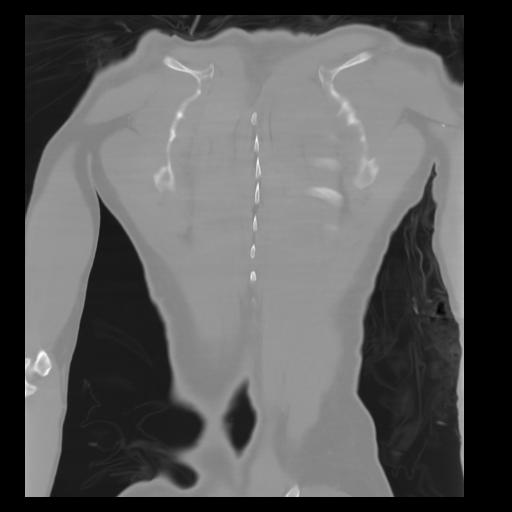

29 CUERPO,CE,Coronal,3.000,CUERPO,Coronal,